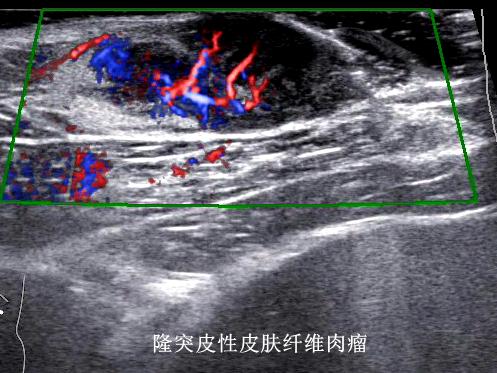

传统皮肤科诊断主要靠眼睛观察、手触摸,或取一点皮肤组织做病理检查,很难直接看到深层的情况。超高频超声(通常指频率在20MHz以上的超声),提供了新的观察维度——20MHz超高频超声可分辨0.1mm的病灶,70MHz超声高频超声可以分辨0.03mm病灶。

通过分析病灶的形态、边界特征和内部血供情况,医生能够更准确地区分炎症性病变、良性增生性病变与恶性肿瘤。